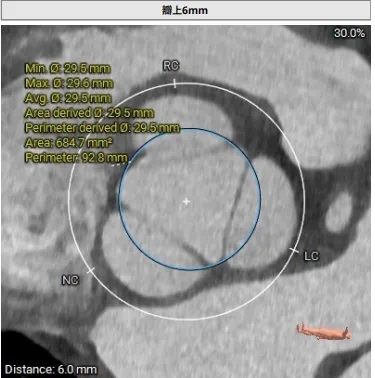

瓣上结构测量

周长77.3 周长径24.6

周长82.8 周长径26.4

周长92.8 周长径29.5

周长98.2 周长径31.3